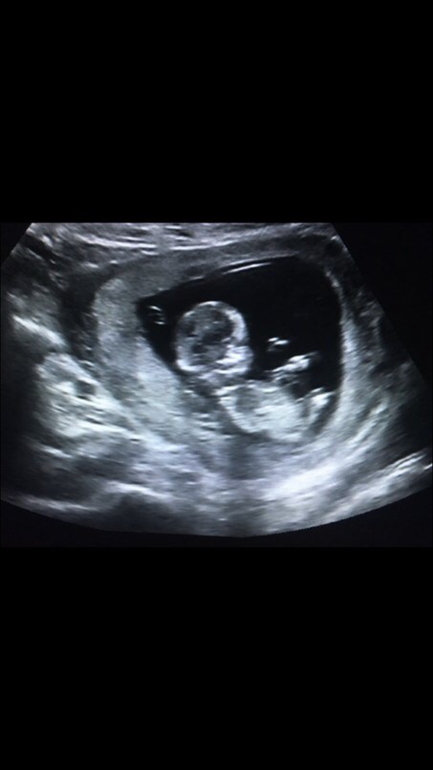

Фото на первом скрининге,разрешили сфоткать с монитора

На УЗИ смотрят развитие плода,самые главные зоны,это копчико теменной размер,воротниковая зона и носовая кость.